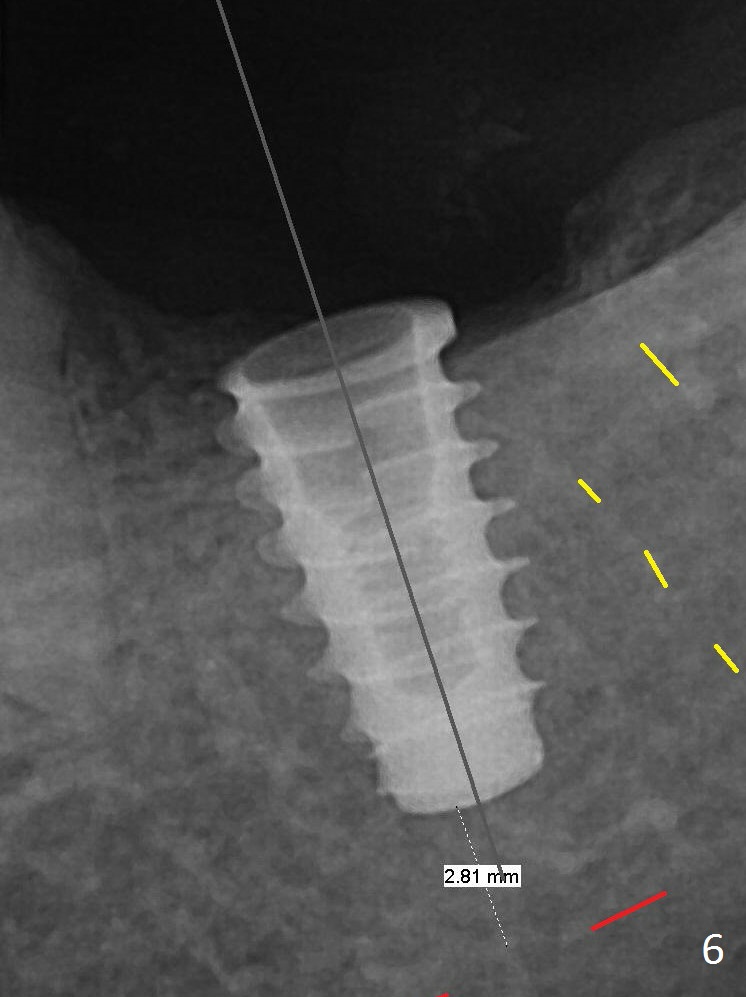

After Marking Bur and 4.3 mm Magic Drill, a 5x9 mm IBS implant is placed with 2.8 mm clearance from the Inferior Alveolar Canal (Fig.6). Following deepening the osteotomy with Final Drill, the implant is placed deeper (Fig.7). The osteotomy happens to be established in the mesial socket, since the distal socket has not completely healed (Fig.6 yellow dashed line). Granulation tissue is removed. Since the lingual crest is lower than the buccal one (Fig.1 B), there is lingual thread exposure after implant placement (Fig.5). The exposed thread is covered by bone graft (autogenous bone, allograft and Osteogen, Fig.5 pink circles). Some of the graft is apparently pushed into the distal socket (Fig.7 yellow dashed line) post GBR and suture. As the implant is placed twice, insertion torque is <10 Ncm (although the implant is stable). A 5x3 mm healing abutment is placed (Fig.7 H). There is no apparent bone loss 4 months postop (Fig.10).